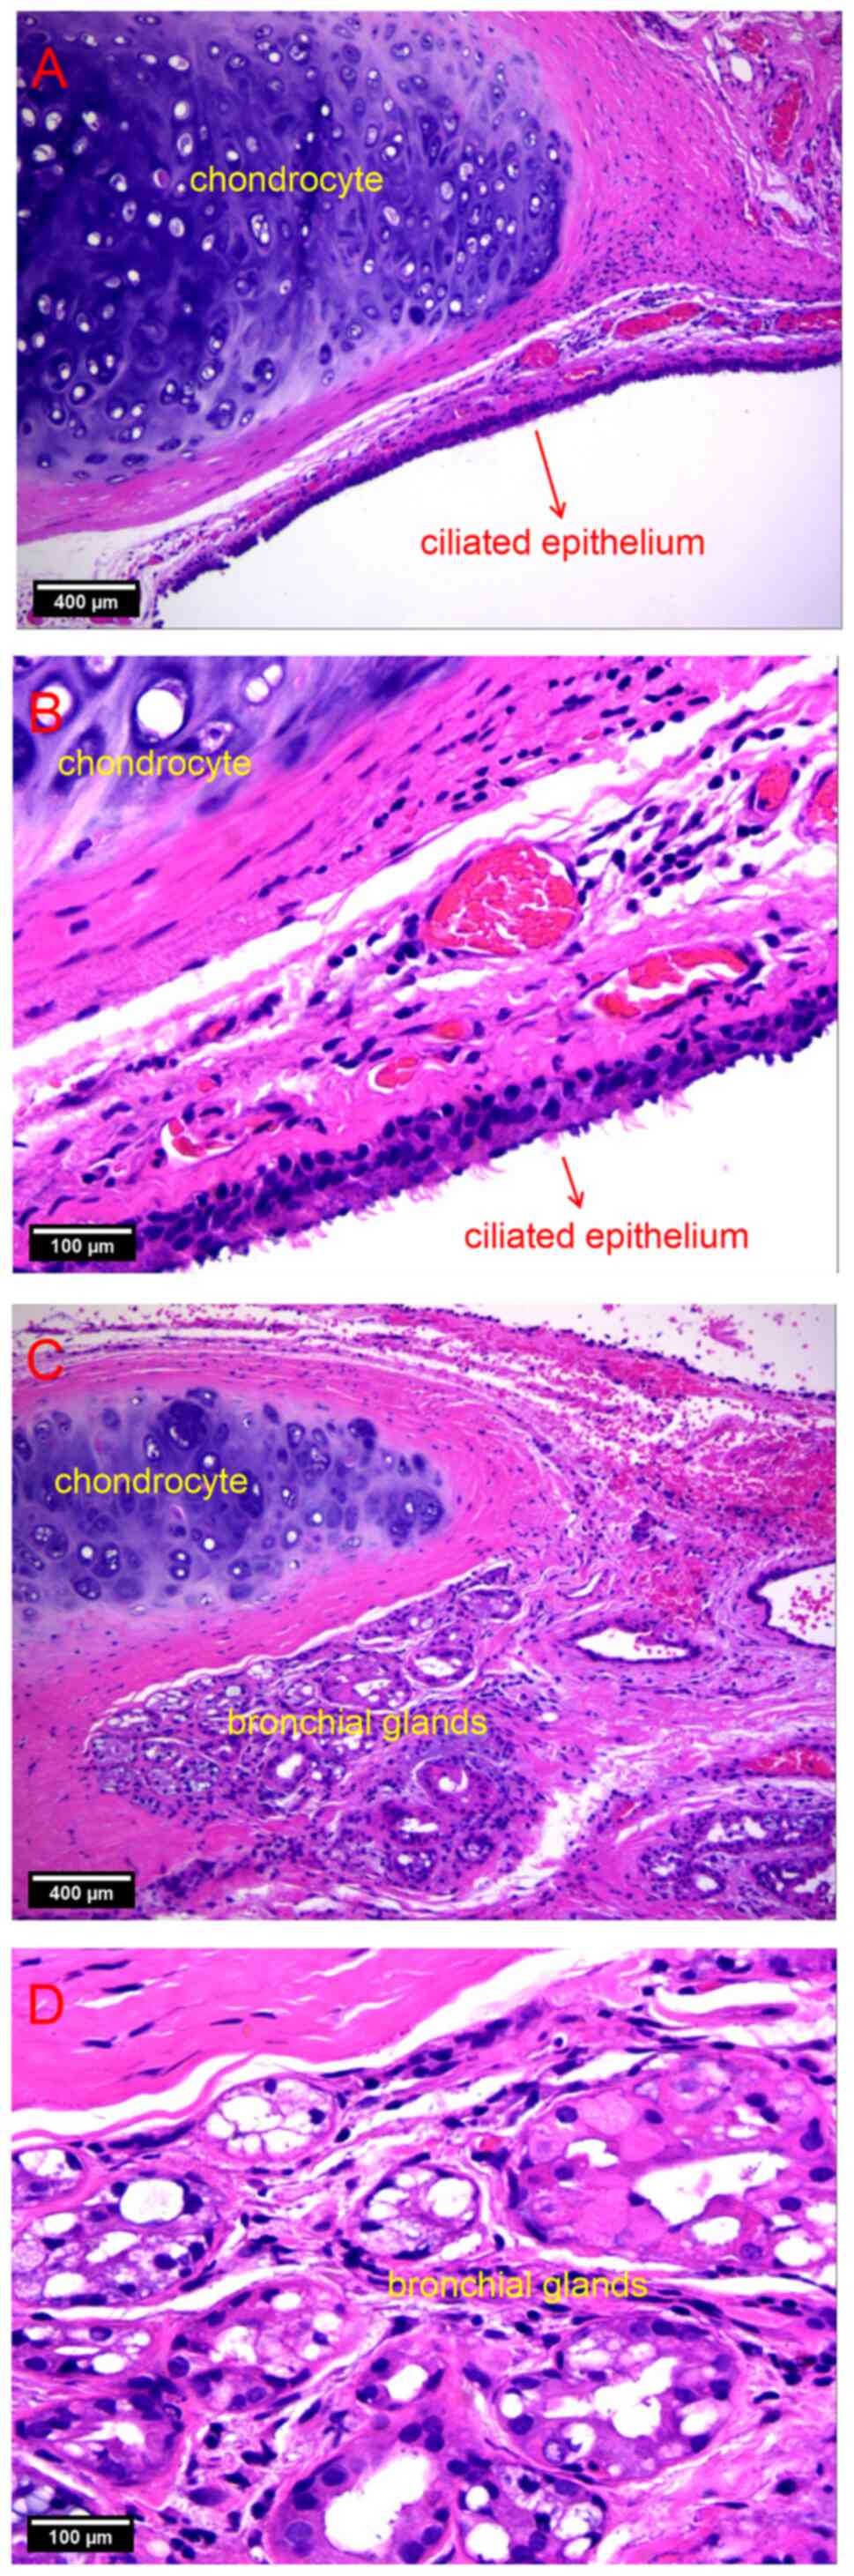

liquid. The cysts were analyzed pathologically by hematoxylin and

eosin staining, the protocols as follows: The tissue of cyst was

fixed in 4% paraformaldehyde for 24 h and then dehydrated and

embedded in paraffin. The specimen was cut into 10-µm slices, then

dewaxed and immersed in hematoxylin solution for 5 min. After

rinsing with water, the slices were stained with eosin Y solution

for 2 min. After dehydration with alcohol and clearing with xylene,

the slices were sealed with neutral resin and prepared for

pathological analysis under the light microscope. The results

revealed that the cyst wall was covered with pseudostratified

columnar epithelium (Fig. 3A and

B). In addition, there were

chondrocytes and bronchial glands but no blood cells or calcium

components in the cyst, which was suggestive of a bronchogenic cyst

(Fig. 3C and D). After surgery, the pain symptoms of

Pathological examination remains to be the gold

standard for detecting bronchogenic cysts (21). The typical pathological finding is

a cyst wall covered with pseudostratified ciliated columnar

epithelial cells. Furthermore, this type of cyst contains cartilage

or bronchial glands without any cell atypia (24). A respiratory epithelial cyst